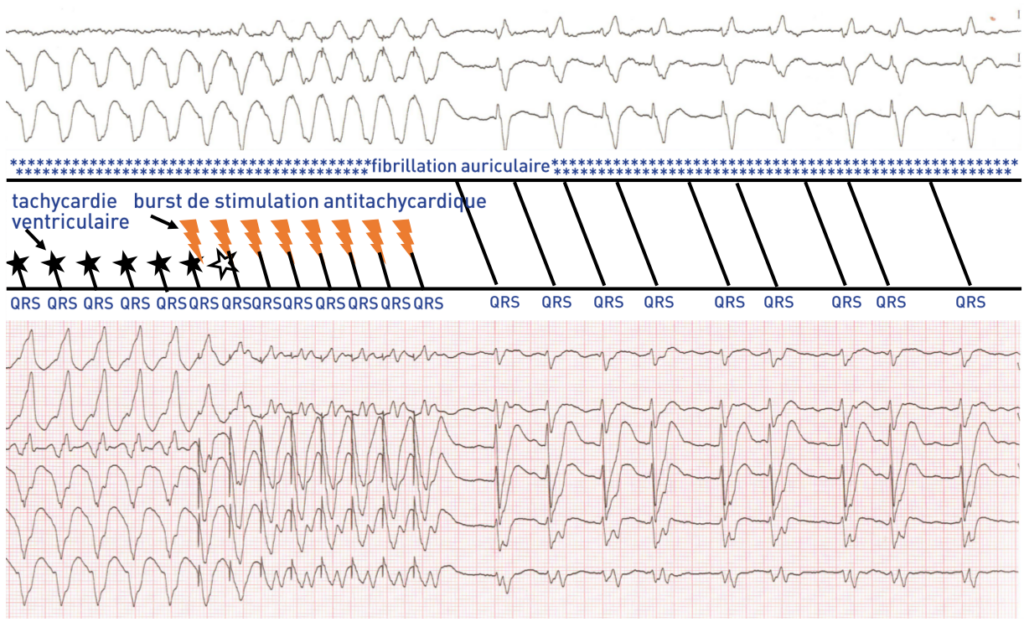

Description tracé

Le patient bénéficie d’un burst de stimulation antitachycardique délivré par le défibrillateur; il permet l’interruption de la tachycardie et met en évidence un QRS spontané très large (différent de celui en tachycardie) et une fibrillation auriculaire; ce patient présentait donc une bitachycardie (fibrillation auriculaire + tachycardie ventriculaire);